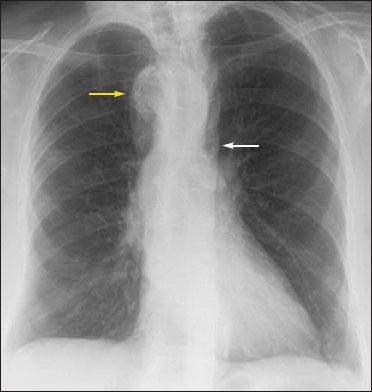

Figure 1 – A chest radiograph showed the absence of an aortic knuckle (white arrow) and a right-sided aortic arch (yellow arrow).

Results of a complete blood cell count and complete metabolic panel were normal. A chest radiograph showed a tortuous right-sided aortic arch but an otherwise unremarkable cardiomediastinal silhouette; the lungs were clear without evidence of focal collapse, consolidation, effusion, or pneumothorax (Figure 1).